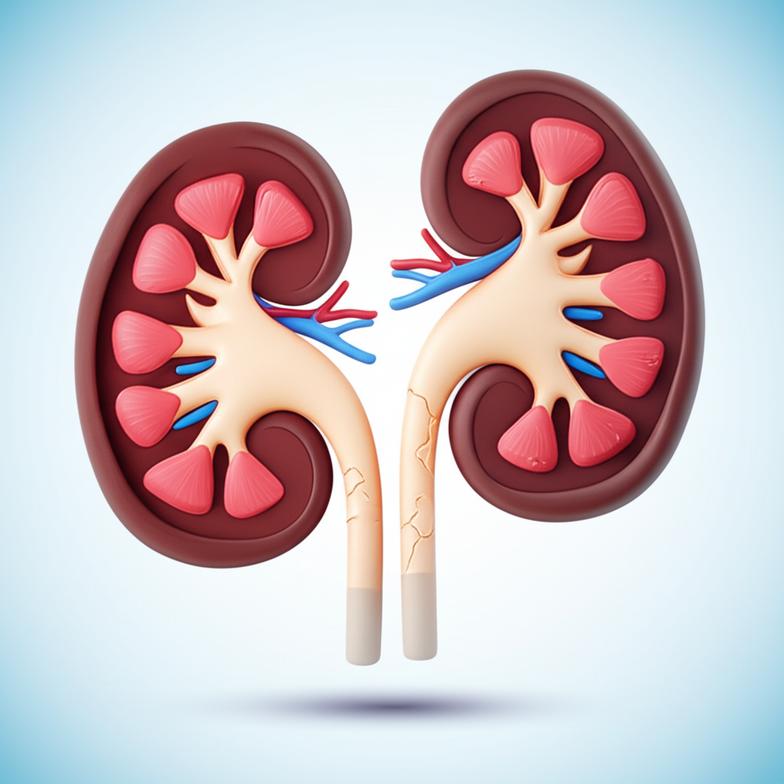

ไตทำงานอย่างไรและสัญญาณเตือนความเสื่อม

ไตสองข้างของเรานั้นเปรียบเสมือนโรงงานบำบัดน้ำเสียอันซับซ้อน แต่ละข้างประกอบด้วยหน่วยกรองขนาดเล็กนับล้านหน่วยที่เรียกว่า “เนฟรอน” (Nephron) ซึ่งทำหน้าที่กรองเลือด ขจัดของเสียส่วนเกิน เช่น ยูเรีย ครีเอตินิน และกรดยูริก ออกจากร่างกายผ่านทางปัสสาวะ พร้อมทั้งรักษาสมดุลของน้ำ เกลือแร่ และความเป็นกรดด่างในเลือด นอกจากนี้ ไตยังมีบทบาทสำคัญในการสร้างฮอร์โมนที่เกี่ยวข้องกับการสร้างเม็ดเลือดแดง (Erythropoietin) การควบคุมความดันโลหิต (Renin) และการรักษาสุขภาพกระดูก (Active Vitamin D)